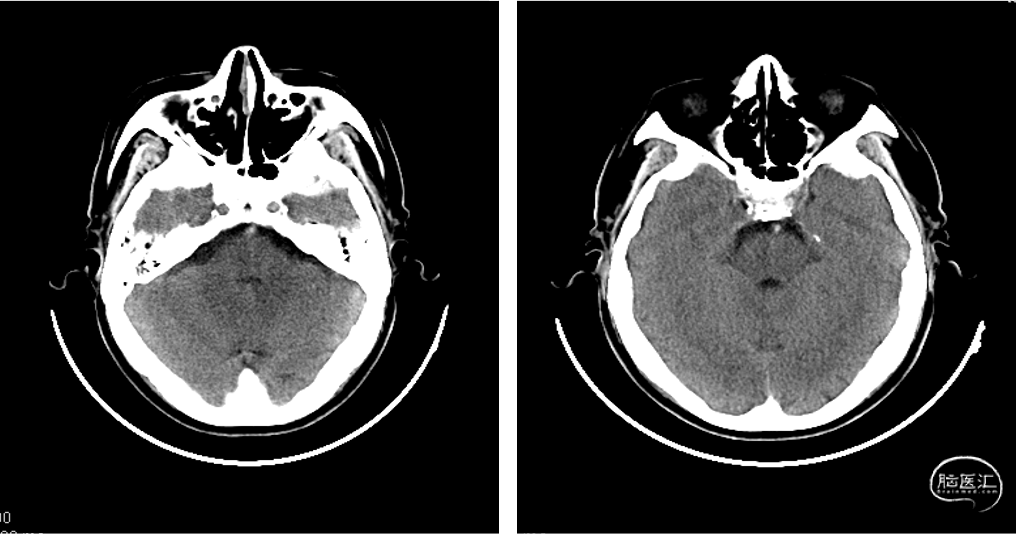

头部CT提示:

1. 双侧基底节区、放射冠区、半卵圆中心、丘脑多发腔隙性脑梗塞,建议MRI检查。

2. 脑白质缺血、脑萎缩。